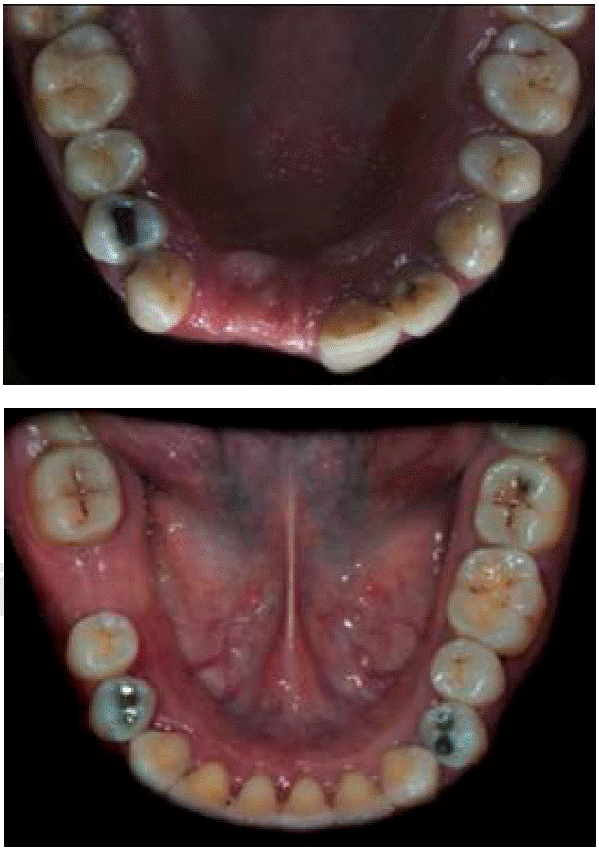

De acuerdo con la nomenclatura de la Federación Dental Internacional (FDI), la paciente tenía caries oclusales en molares y premolares, caries de cíngulo, restauraciones con amalgama, fractura en distal y caries en cíngulo del OD 23 y cuatro dientes ausentes (Figuras 3AyB). De igual forma mostró cálculo dental y tejido gingival inflamado.

Se realizó un curetaje en la zona receptora, eliminando tejido de granulación con el fin de tener un nicho receptor limpio y un raspado radicular de los órganos dentales adyacentes. Se probó la lámina ósea fina de 25 × 35 mm y se recortó para adaptarse a la zona receptora (Figura 7). Se cribó el tejido óseo en la superficie vestibular del defecto con motor quirúrgico y contrángulo recto con fresa de carburo de bola del número 2 y se irrigó con suero fisiológico. El xenoinjerto Gen-Os se preparó con suero fisiológico estéril en un godete metálico estéril y fue llevado a la zona del defecto óseo (Figura 8). Una vez rellenado el defecto óseo, se liberó el colgajo hasta que llegara al tercio incisal de los órganos dentarios 12, 11 y 23. A continuación, se hidrato la lámina ósea durante aproximadamente cinco minutos en solución fisiológica hasta obtener la consistencia de plasticidad deseada. Fue adaptada en la zona receptora (Figura 9) y fijada e inmovilizada con sutura de aguja triangular no traumática Vicryl 4’0s. Se realizó la síntesis de los tejidos suturando con Nylon 4’0s empleando la técnica de colchonero vertical y algunos puntos de sutura simples. También se hizo un lavado con suero fisiológico y se limpió la zona quirúrgica con gasas estériles. Se ajustaron provisionales de tal manera que los pónticos no contactaran con la zona en regeneración.